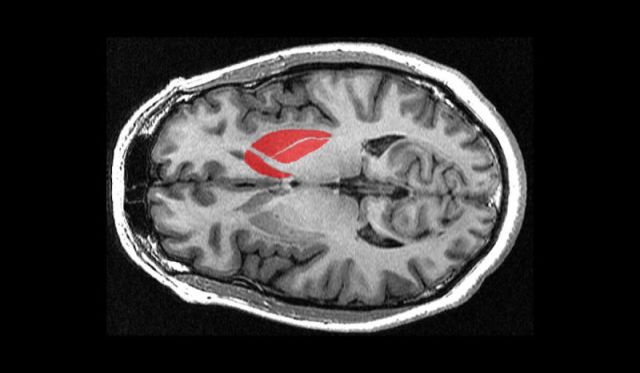

Takahashi and his colleagues will inject dopamine-producing neural progenitor cells—derived from induced pluripotent stem cells (iPSCs) from healthy adult donors—into Parkinson’s patients’ brains. Approximately 5 million cells will be injected into the patients’ striatum (in red above), the primary brain region implicated in the disease.